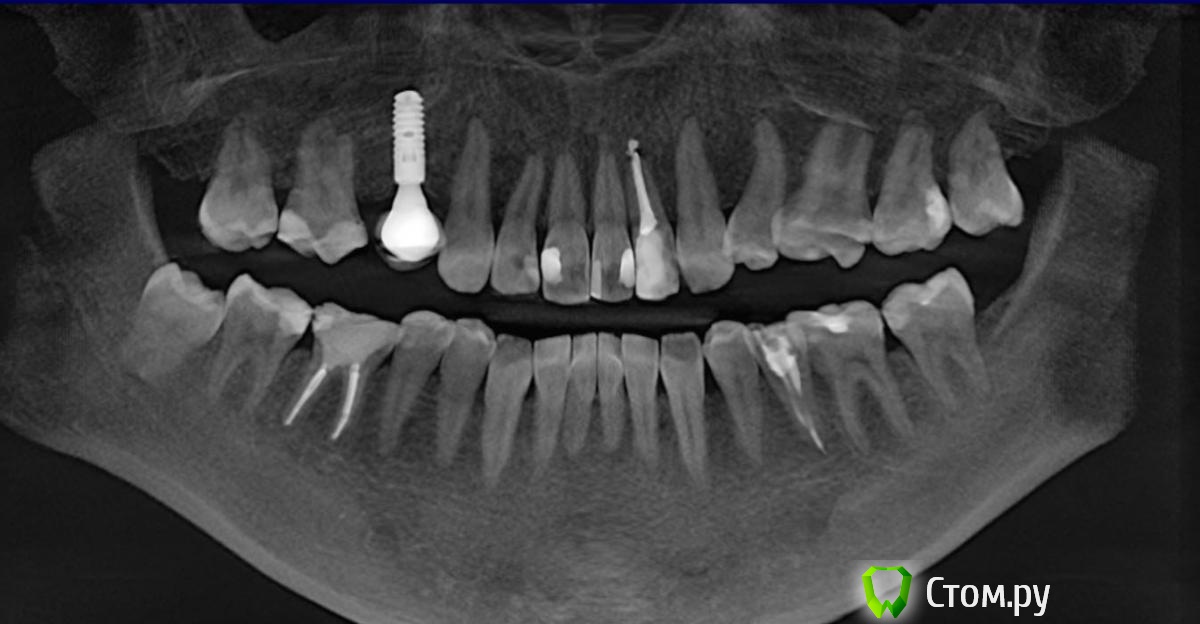

dr-krasnov Опубликовано 23 сентября, 2014 Поделиться Опубликовано 23 сентября, 2014 http://s011.radikal.ru/i316/1409/3a/0034e3a4961e.jpg в 1 квадранте все ок. http://s019.radikal.ru/i603/1409/19/1bbf0e29b99a.jpg В 46 периодонтит. Ссылка на комментарий

Lyuba Опубликовано 25 ноября, 2014 Автор Поделиться Опубликовано 25 ноября, 2014 (изменено) 16 зуб (рядом с имплантом)... заменена старая пломба. Описание рентгенолога: пломба прилегает к рогу пульпы. карманы на половину длины корней.небольшое разрежение ткани периодонта вдоль корней, в т.ч. верхушки.см. рентген доктора краснова выше.изначально предполагалось, что ноющие боли из-за "просветов" между соседними зубами и 16м зубом и коронкой на импланте, куда забивалась пища. Просвет убрали, коронку временно сняли, пломбу переставили, зуб живой, на раздражители не реагирует, внешне, как сказала пародонтолог, все замечательно, а ноет еще больше... что делать? ведь, если нерв живой и проблема в периодонте, то и удаление нерва проблему не решит? может все-таки есть какие-то средства - витамины, полоскания, которые помогут несчастным зубам "выстоять" ? циклоферон поколоть? Изменено 25 ноября, 2014 пользователем Lyuba Ссылка на комментарий